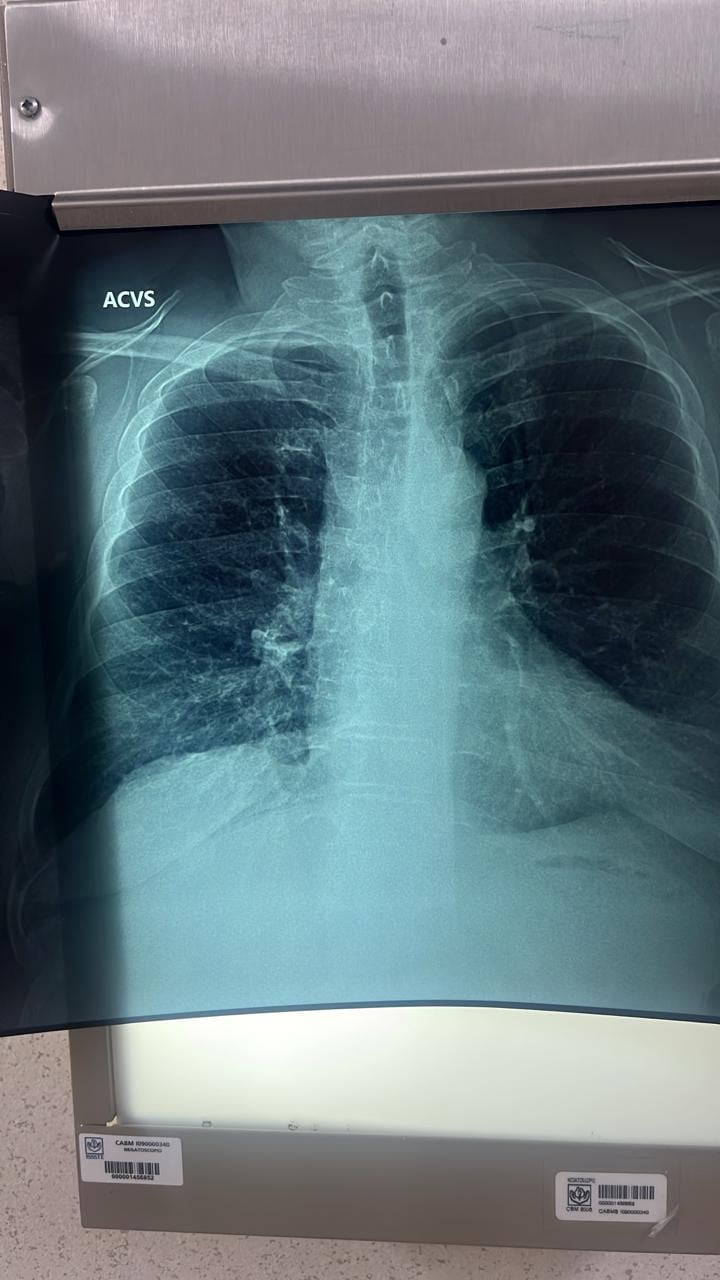

El neumólogo Jorge López de la Cruz, de la Clínica de Especialidades “Indianilla”, detalló que la EPOC es un padecimiento que reduce el flujo del aire en los pulmones, provocando inflamación, obstrucción de bronquios y daños severos en la respiración.

Jorge López explicó que en casos avanzados, la enfermedad puede generar enfisema pulmonar, es decir, la destrucción de las paredes de los alvéolos que impide que los pulmones tomen oxígeno y eliminen dióxido de carbono de manera adecuada.